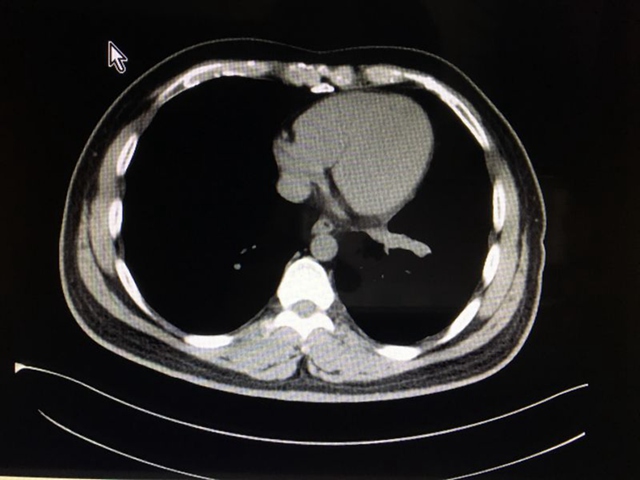

治疗中期的CT影像: